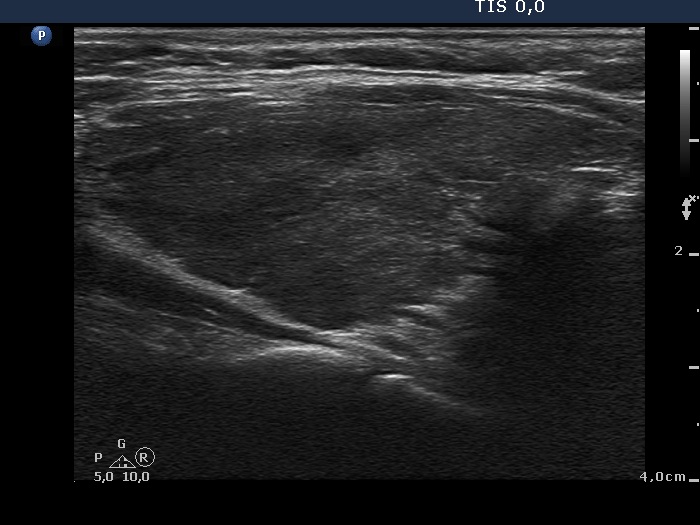

Consecutively operated patients with autoimmune thyroid disease - case 7 (1673) (ultrasonographic picture 5)

Left lobe, longitudinal scan.